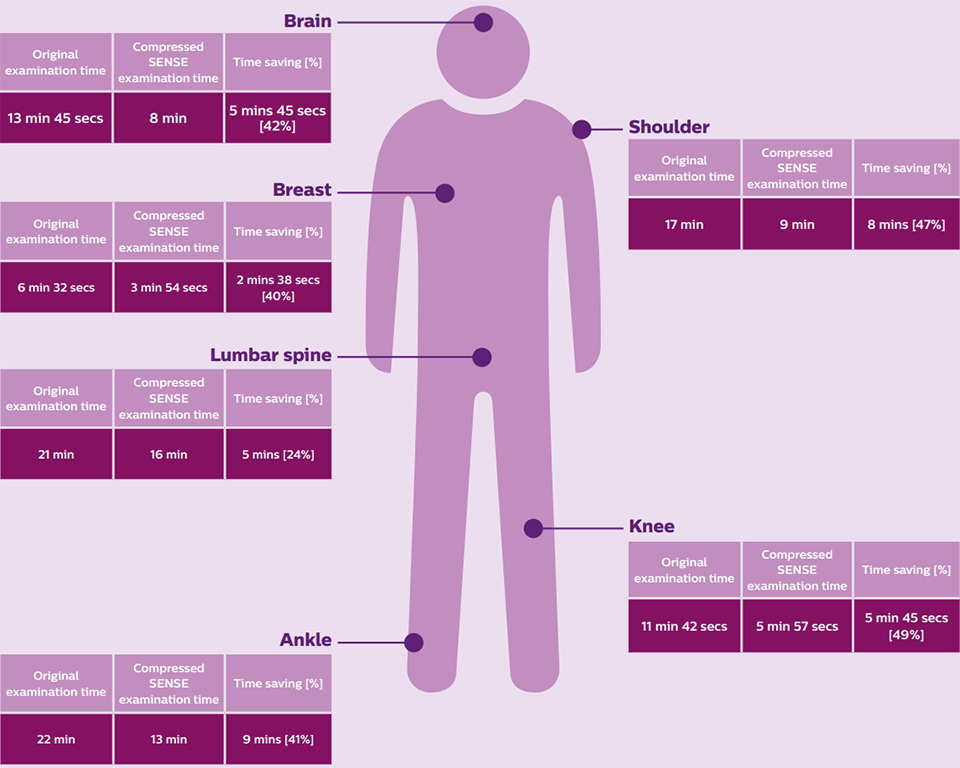

In September 2018, Cobalt was the first imaging facility in the UK to install Compressed SENSE in a clinical setting. Over a three month trial period, the team has been able to scan an additional 17-20 patients per week compared to the same period in the previous year, using the same Ingenia 3.0T scanner. The time gain with Compressed SENSE was also used to increase spatial resolution in anatomies where this matters, for instance in breast imaging.

“Cobalt saw its diagnostic imaging services reduce their MRI examination times by up to 30–50%, accommodating up to 20 additional patients per week as a result.”

The team were able to scan an additional 17–20 patients per week, compared with the same period in the previous year. The increased throughput meant that the staff had to be more prepared in terms of moving the patients through the system efficiently.

“I would definitely say that throughput has been helpful to our breast list. Prior to Compressed SENSE we were scanning up to seven patients, we’re now able to scan up to nine patients within the same time period,” says Zoe Wray.

The time gain with Compressed SENSE was also used to increase resolution in order to help radiologists identify the tumor characteristics more confidently which may be used for a more personalized treatment. For example, in breast imaging, resolution is crucial for visualization of very small lesions. Compressed SENSE allows to scan thinner slices, allowing a 3D isotropic sequence which can provide increased diagnostic confidence for the radiologists.